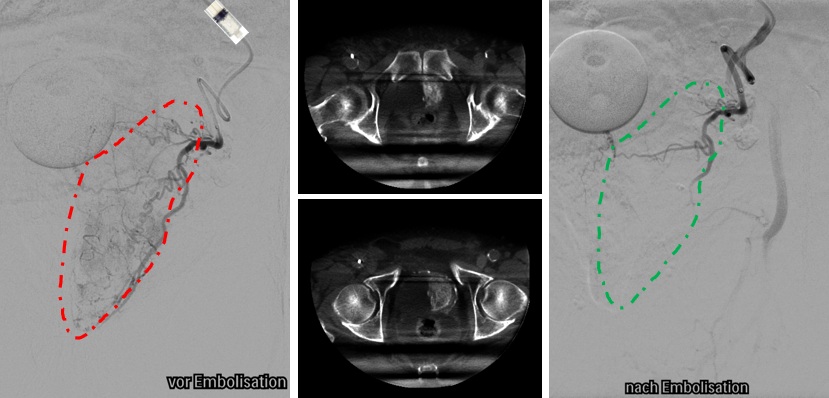

Moderne Hilfe bei chronischen Knieschmerzen: Genikulararterienembolisation

6. März 2025 - Das Institut für Radiologie und Neuroradiologe am Klinikum Aschaffenburg hat vor kurzem erfolgreich die schonende Behandlung der Kniegelenksarthrose, die sog. Genikulararterienembolisation (GAE), etabliert. Weiterlesen